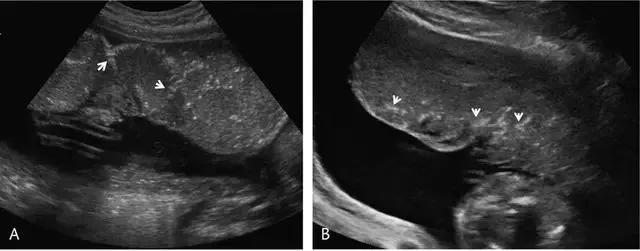

正常胎盘呈圆形,边缘较薄,直径为 15~20 cm,厚度为 2~4 cm。Hoddic 等人报道,在整个孕期里,胎盘厚度(毫米)大致与妊娠周数相同,但应<4 cm。胎盘随妊娠进展而逐渐出现钙化,从而可对胎盘分级(0 级-3 级),同时这种变化与胎儿成熟度相关联,可预测不良胎儿结局(图 3)。

图 3 A 为孕 35 周时正常胎盘的矢状面观,可见绒毛膜板外侧、沿着基底板分布的「点-线状」钙化;图 B 为先兆子痫孕妇 25 周时的胎盘横切面观,显示血管区域的线样过早钙化(箭头)

各个胎盘分级之间的发展变化并不显著 ,也无重要的临床意义,但若在足月之前胎盘发生钙化或成熟则会增加胎儿和孕妇不良结局的风险,如早产、低体重儿、Apgar 评分低、新生儿死亡、孕妇产后出血、胎盘早剥等。作者建议,如果 27 周前发现 1 级胎盘、32 周前发现 2 级胎盘、34 周前发现 3 级胎盘,则应进行密切的临床及超声随访。